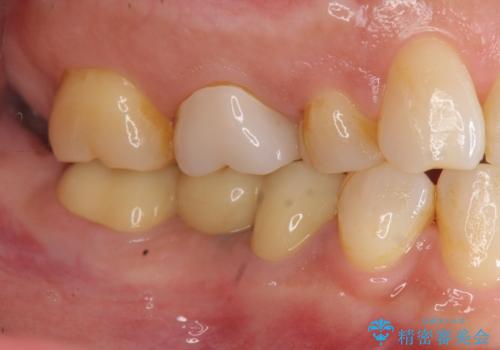

「ブリッジのところで噛むと痛い」 神経組織が原因の咬合痛

- 「以前治療して装着した右下のブリッジの部分で噛むと痛い、何もしなくても痛い」、と治療を希望され来院されました。

X線写真より歯の神経組織が壊死し、根尖周囲に病変を作り透過像を呈している状態でした。

咬合痛の原因となっている右下第2大臼歯の根幹治療を行ったのち、強度に優れるフルジルコニアクラウンによる咬合機能回復を計画します。

- 28.6万円(仮歯・フルジルコニアクラウン×3・ファイバーコア)費用は治療当時の料金となります